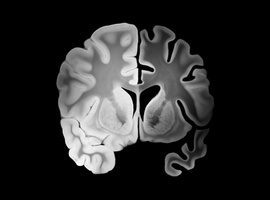

Overmatig alcoholgebruik en hersenletsels: rechtstreeks verband met hyaline arteriolosclerose en cognitieve achteruitgang

Chronisch alcoholgebruik is een bekende risicofactor voor verschillende neurologische, cardiovasculaire en hepatische aandoeningen. De specifieke neuropathologische mechanismen die alcoholgebruik koppelen aan verslechterde hersenfuncties zijn echter nog niet volledig...